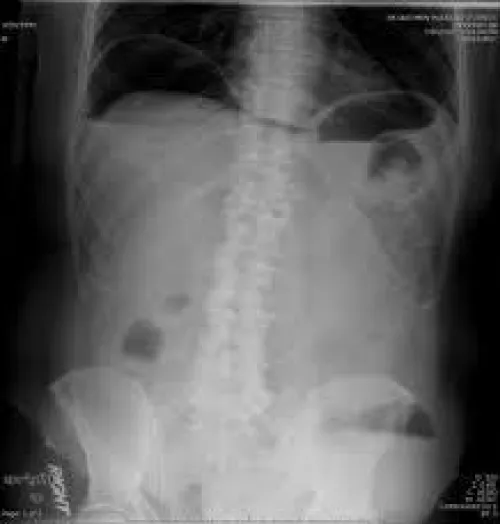

She had hemoglobin of 9.4 g/dl(MCV 83.1, MCh 28.8) and a white cell count of 5.87 × 109 with N:48%, L:45%. As her pain worsened, repeat abdominal examination revealed obliteration of upper border of liver dullness and absent bowel sound. Serum lipase, random blood sugar, renal and liver function tests were non conclusive. X-ray abdomen in erect posture antero-posterior view showed free air under both the domes of the diaphragm (Figure 1).She was kept nothing per oral. Parenteral fluid, analgesics and broad-spectrum antibiotic were commenced. She was also transfused with 1 unit of packed cells. An urgent ultrasound abdomen was arranged, which revealed a heterogeneous collection in the subhepatic region and multiple enlarged mesenteric lymph nodes. A diagnosis of likely perforated appendicitis was made and she underwent an emergency laparotomy.